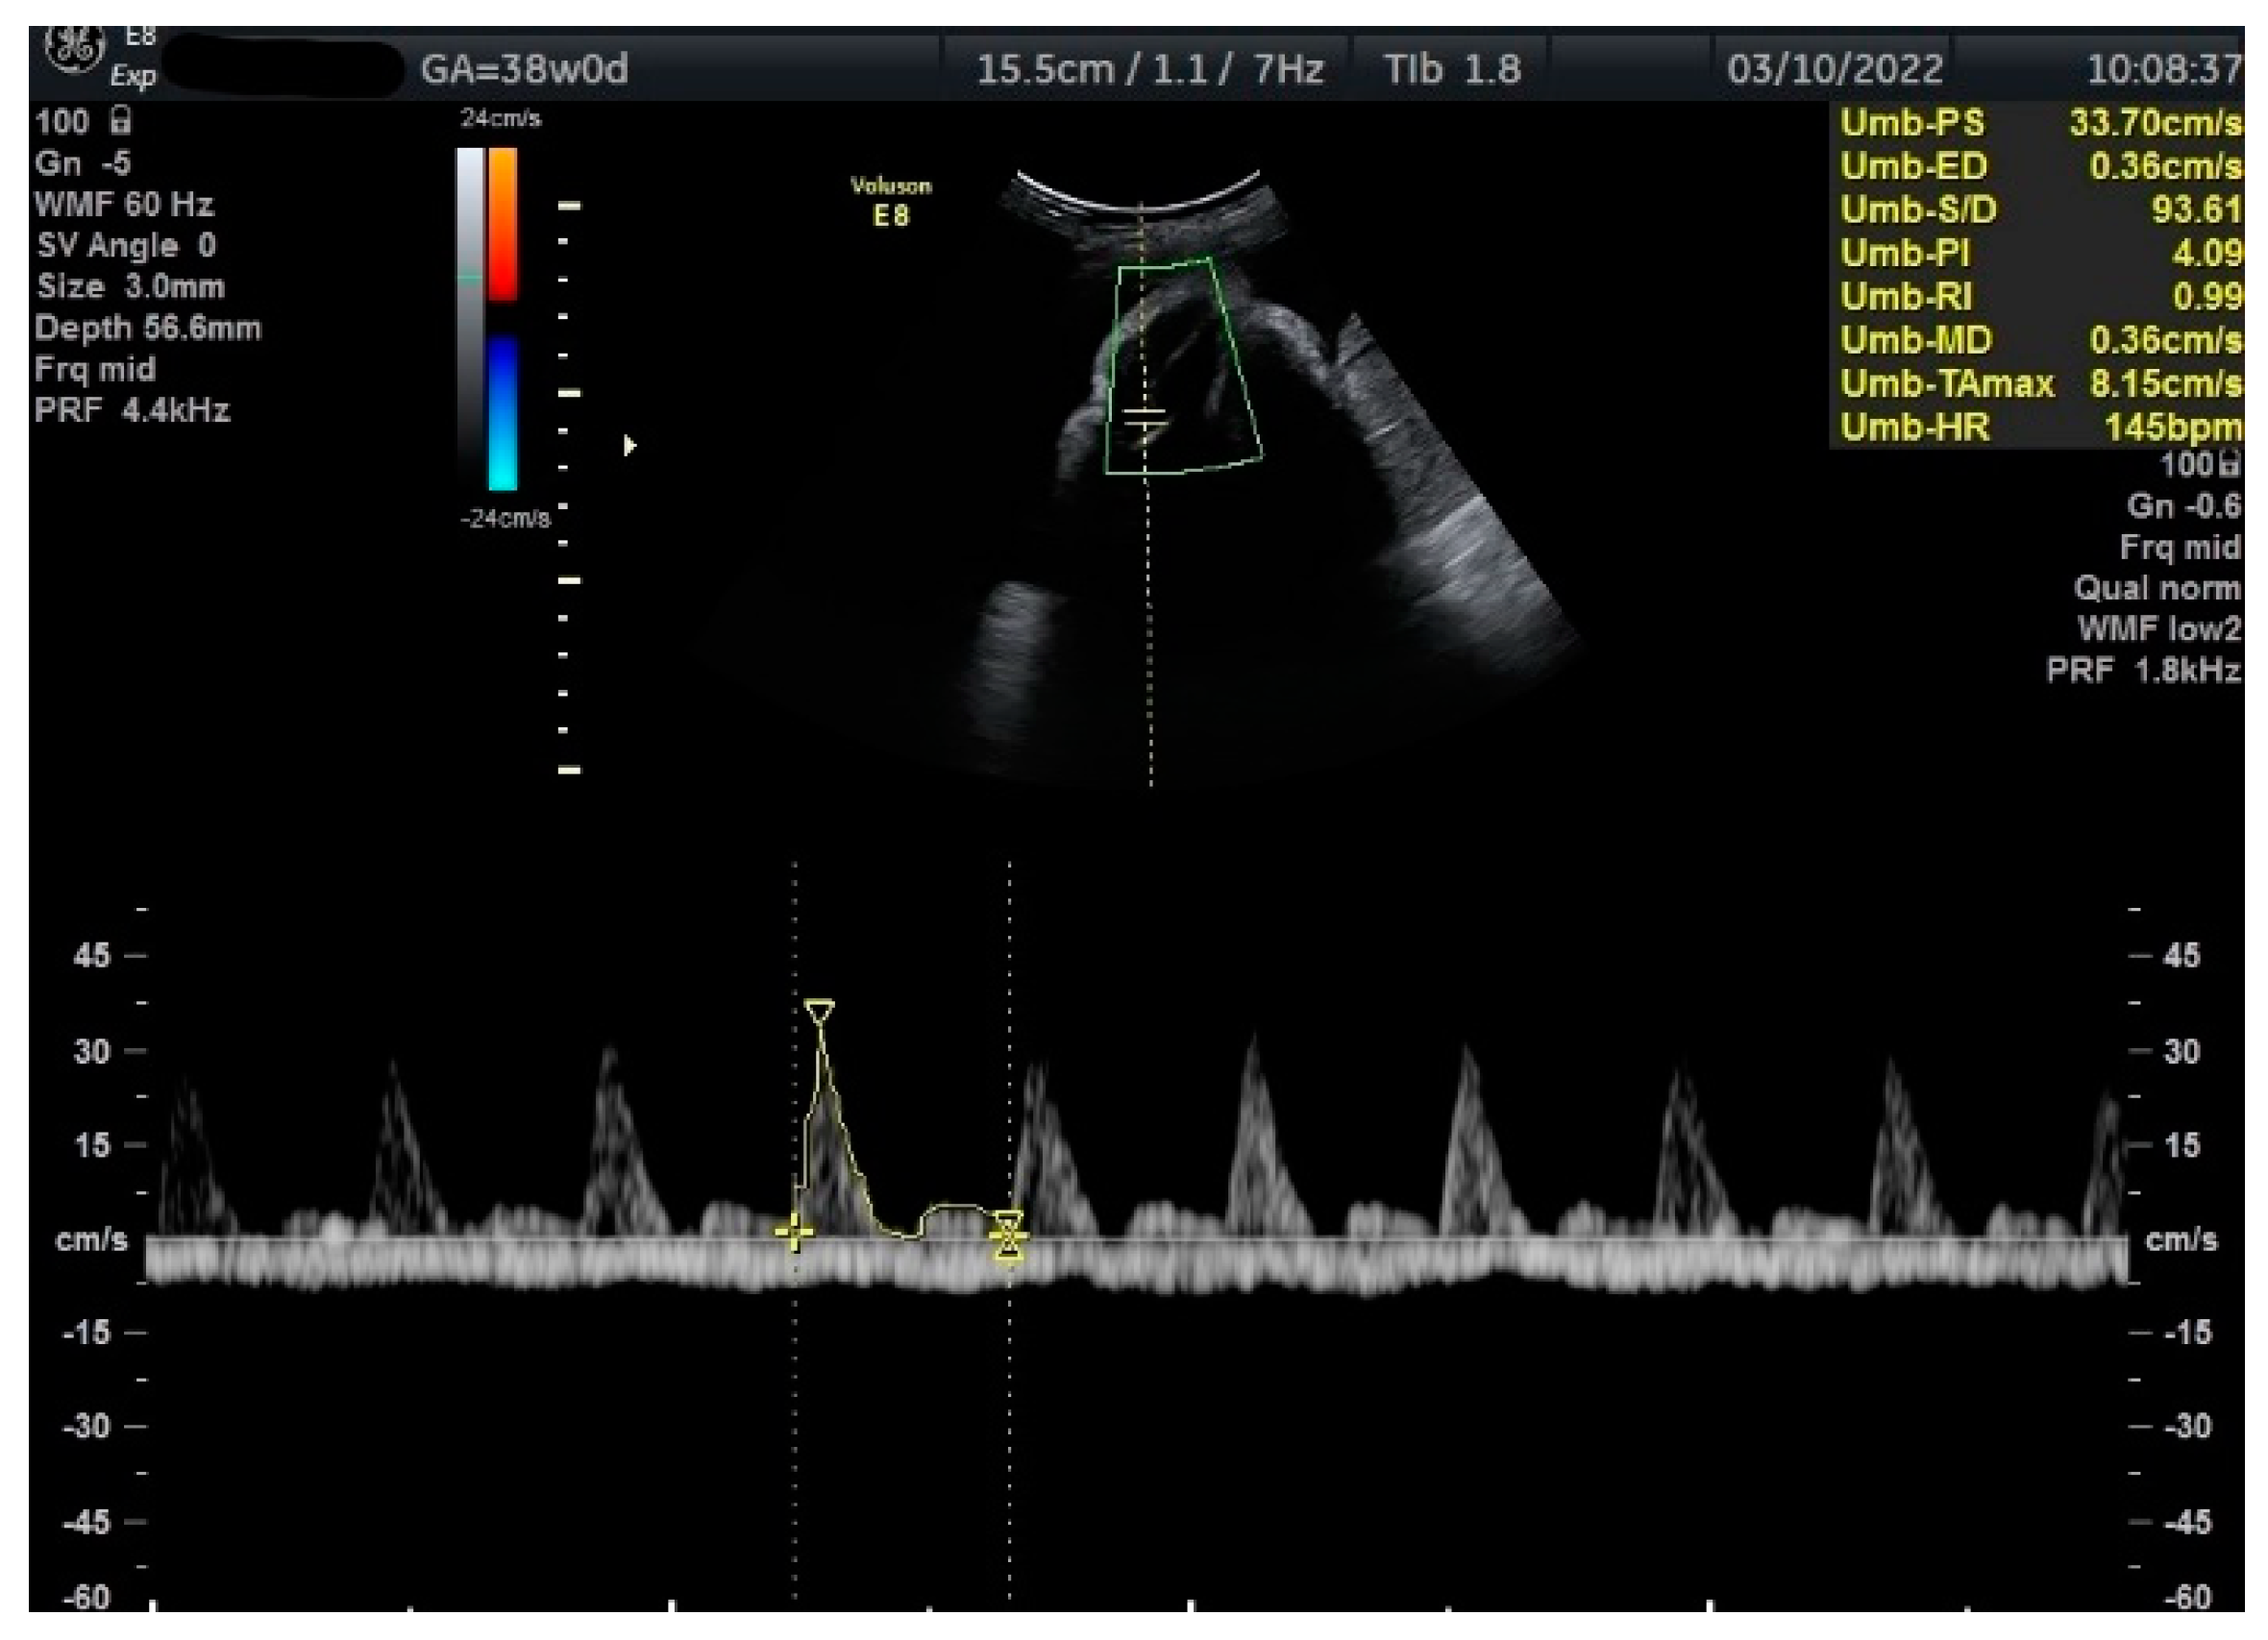

Figure 2.

Doppler measurement at 38 + 0 weeks of normal TA-PI (measured manually).